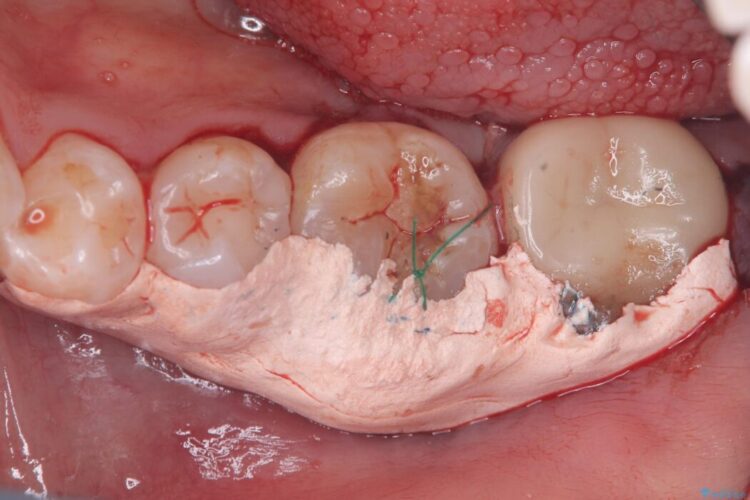

保存が難しい左下6番を抜歯し、左下8番(親知らず)を抜歯窩に移植しました。歯牙移植後の動揺防止のため暫間固定を行っています。

また移植後2週間経過時点で根管処置が必要となります。